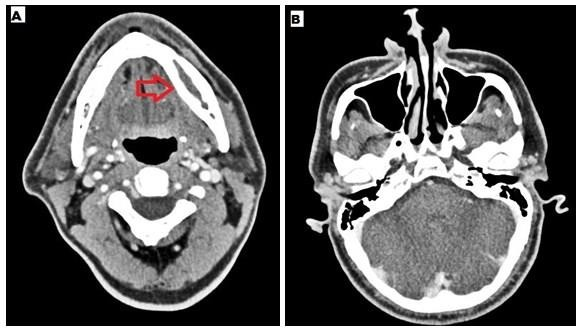

Case 1: He was a 39 year old male presented with left jaw pain for two months. He was diagnosed with Covid-19 pneumonia and required oxygen with dexamethasone at a dose of 6mg twice a day followed by once a day for total 14 days eight months ago. Due to his jaw pain he consulted dentist before coming to our instituition and underwent left 3rd molar extraction. Following the procedure his symptoms did not improve rather worsened. Pain and swelling increased gradually and there was oozing from the tooth extraction site. He did not have any sinus symptoms and underwent CT scan which revealed left mandibular osteomyelitis (Figure 1). No sinus tenderness was present and sinus endoscopy showed normal mucosa. HbA1C was 9.2%. Debridement of left mandible with extraction of corresponding molars was done. Histopathology from the debrided tissue showed aseptate, broad fungal hyphae with obtuse angle branching with bony and angioinvasion characteristic of mucorales (Figure 2). However fungal culture was negative. He was treated with 2 weeks injection amphotericin - b lipid emulsion which he tolerated well without any toxicity.

Figure 1 A- CT mandible - left mandibular osteomyelitis with expansion of the cortex, B- CT paranasal sinuses – normal.